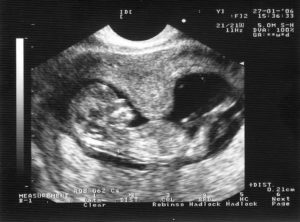

Для диагностики гипертонуса используется ультразвуковое исследование, при проведении которого может быть выявлен гипертонус задней стенки матки, а также передней. Однако, этот признак не всегда может говорить об угрозе прерывание беременности. Матка может прийти в тонус в ответ на прохождение ультразвуковой волны через ее стенку.

Также на ультразвуковом исследовании при выполнении цервикометрии (измерение длины шейки матки) диагностируется истмико-цервикальная недостаточность (укорочение шейки матки, открытие ее внутреннего зева).

Ультразвуковое исследование с допплерометрией даёт возможность детально подойти к диагностике. Определяется распространённость гипертонуса, наличие либо отсутствие ретрохориальной гематомы, оценивается кровоток в сосудах матки и плода.